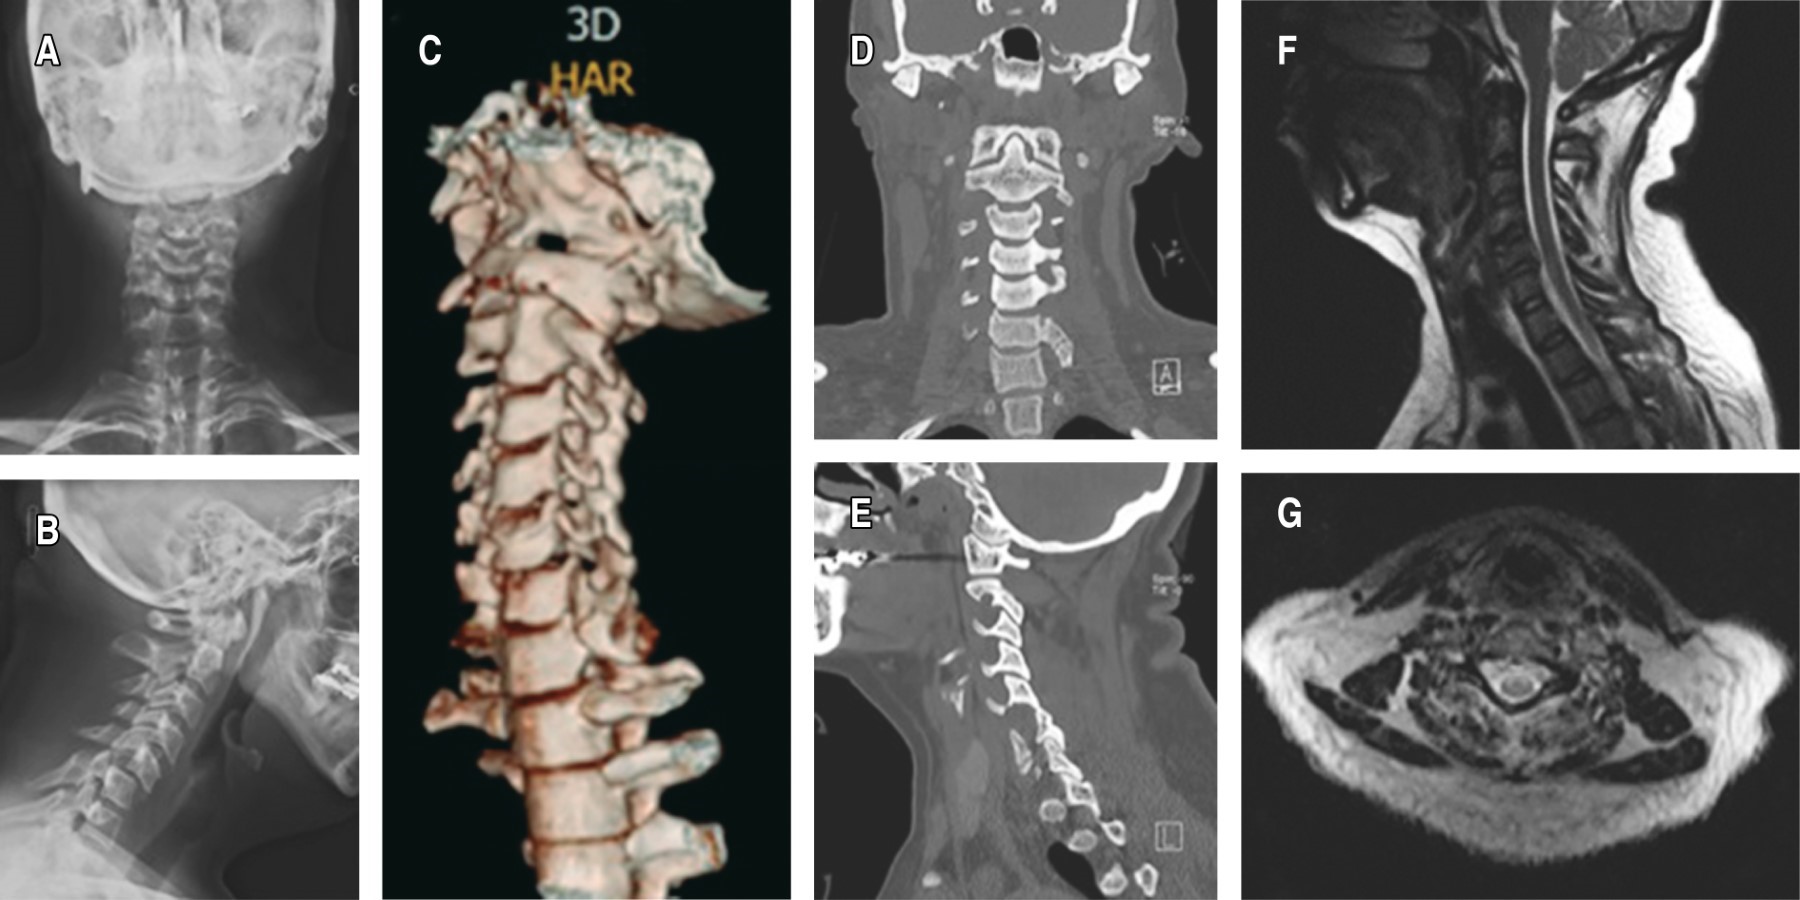

Se trata de paciente masculino de 26 años de edad que presenta accidente automovilístico por choque frontal, ocupa el asiento de copiloto, saliendo expulsado a través del parabrisas al no usar cinturón de seguridad, con pérdida del estado de alerta; es atendido de manera inicial por personal paramédico y es trasladado a medio particular en donde se realiza protocolo ATLS y valoración por cirujano de columna vertebral. A la exploración física con escala de coma de Glasgow 14/15, dermoabrasiones múltiples en cara, antebrazo y pierna derecha, dolor cervical en línea media, extremidades torácicas con fuerza muscular 3/5 de C5-T1, sensibilidad bilateral 1/2, ROTS +/+++, control de esfínteres, extremidades pélvicas fuerza muscular 1/5 de L2-S1, sensibilidad derecha 1/2 con cambios termoalgésicos en extremidad torácica izquierda, ROTS +/+++. Con base en los estudios de imagen iniciales se establece diagnóstico de fractura en lágrima AO C5-C6:C (N1;M2) ASIA C con contusión medular y lesión de complejo ligamentario posterior SLICS 6 (Figura 5).